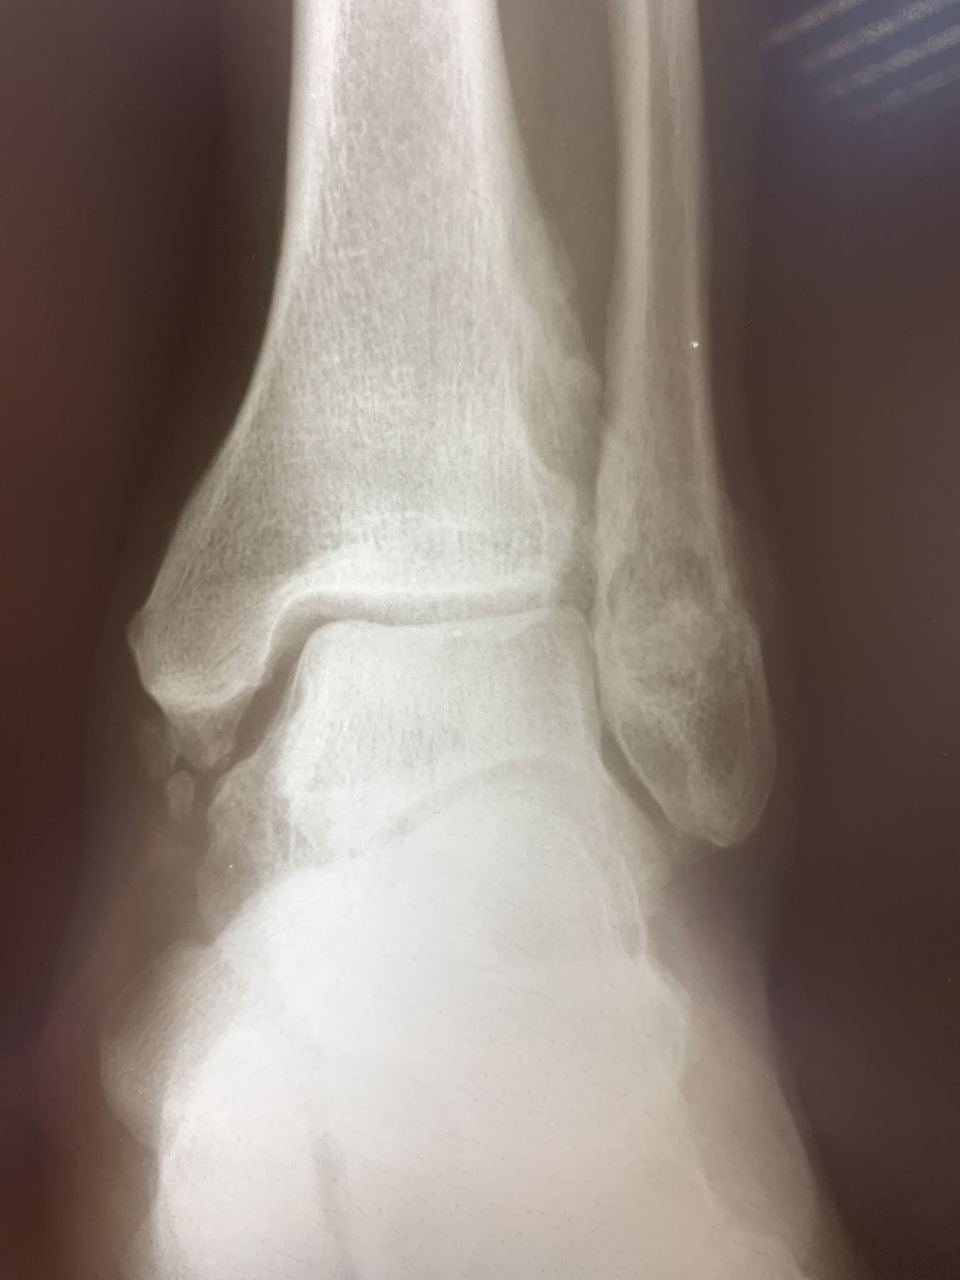

Коллеги, похоже на образование или посттравматическая деформация?

Энходрома может